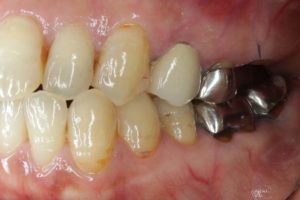

- 術前

- 術後

- インプラント手術直後のレントゲン

長い間お疲れさまでした。この方は、前歯に審美的なインプラントを入れるため、抜歯後4ヶ月待ち、仮歯で歯肉が成熟するのを数が月待っていたりした為に、完成まで時間がかかってしまいました。

虫歯治療などは短期間で終えることができるのですが、歯ぐきをいじり出すとどうしても治癒期間が必要となり長くなってしまいます。それもこれも奇麗な仕上がりのために欠くことのできないものです。何卒ご容赦を!